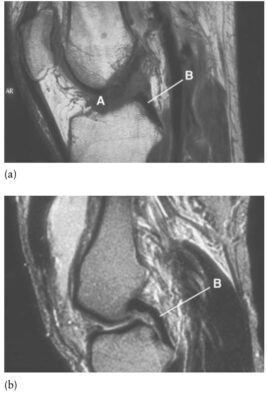

LIÊN HỆ X QUANG KHỚP GỐI

Ghi chú viết tắt:

- A = Anterior cruciate ligament; ACL, dây chằng chéo trước

- B = Posterior cruciate ligament; PCL, dây chằng chéo sau

- Dây chằng chéo trước (ACL, anterior cruciate ligament) tạo cản chính (85%) vận động ra trước của xương chày so với xương đùi. ACL dài hơn PCL 40%. Các phần khác nhau của ACL căng ở tư thế gối khác nhau nhưng nói chung ACL được xem là căng ở tư thế gối duỗi.

- Dây chằng chéo sau (PCL, posterior cruciate ligament) tạo cản chính (95%) vận động ra sau của xương chày lên xương đùi. Nó căng tối đa ở tầm gập gối 45° đến 60°. PCL được xem là căng ở tư thế gối gập. Cả hai dây chằng chéo làm vững, hạn chế xoay, và gây trượt của các lồi cầu lên xương chày khi gập. Chúng cũng đem lại một phần làm vững chống lại lực vẹo trong và vẹo ngoài.